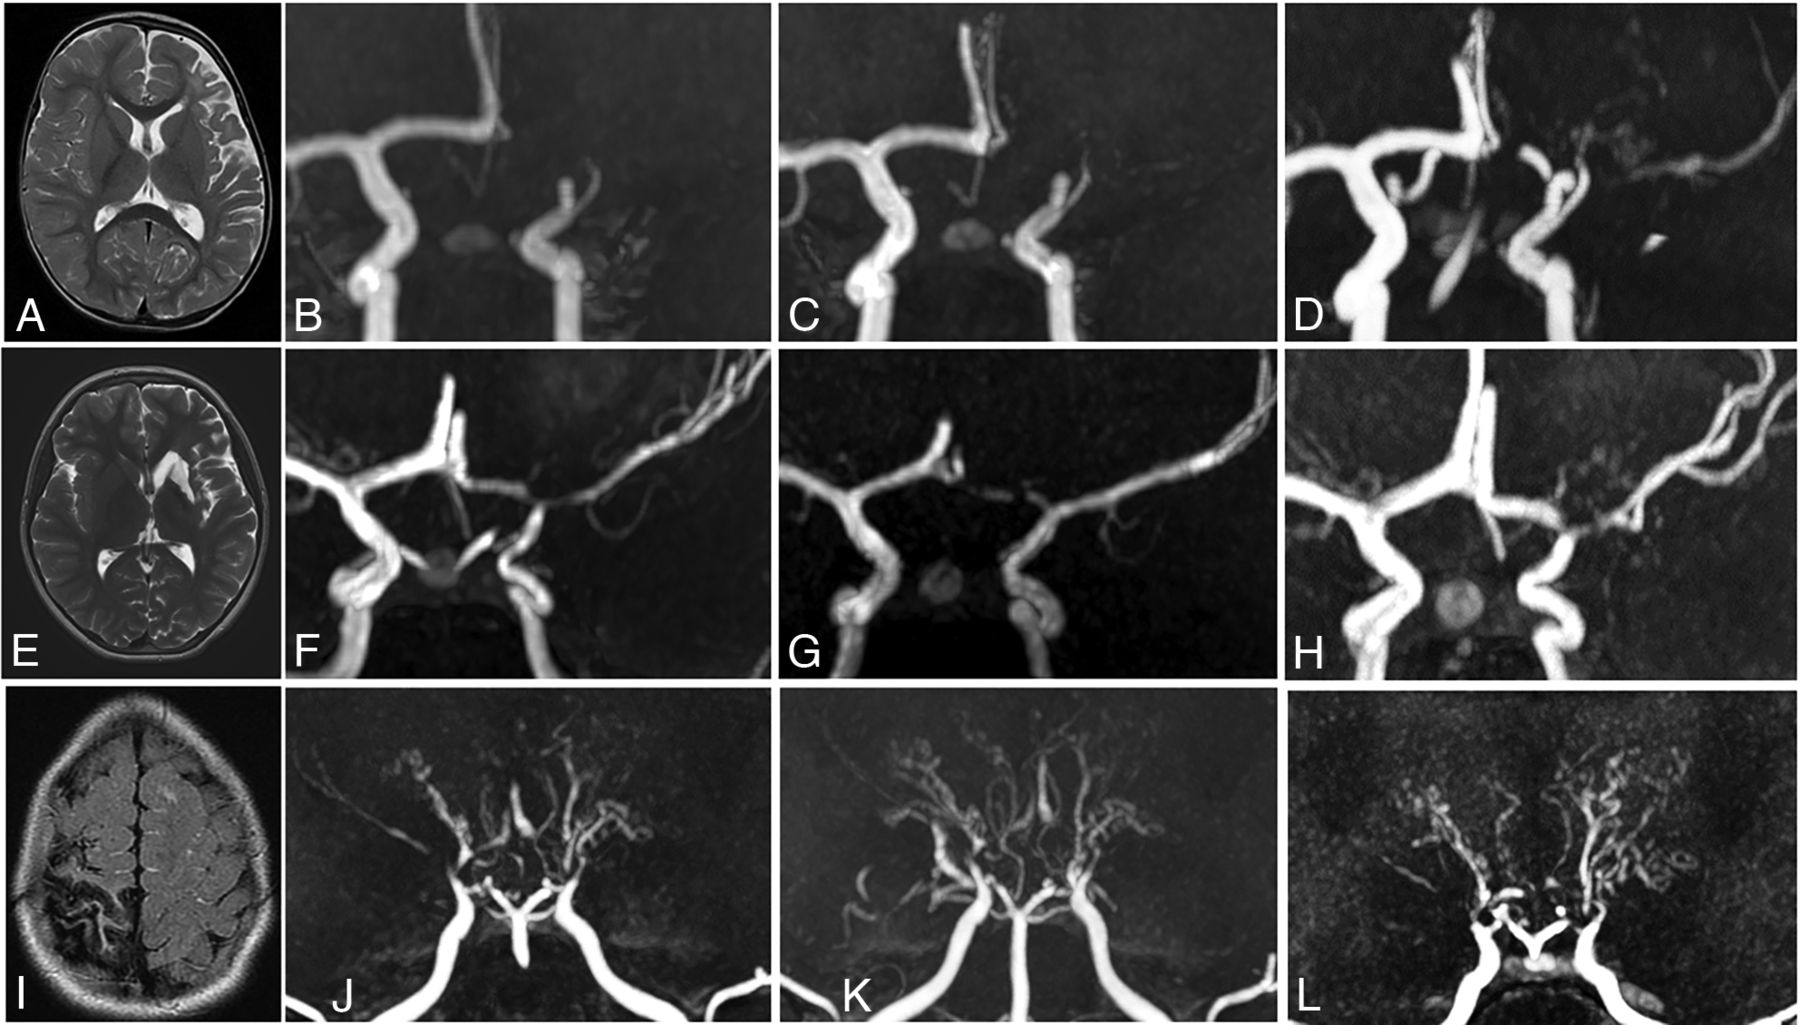

Patterns of angiographic evolution in patients with FCA and U-PS anastomotic bridge development, compared with Moyamoya angiopathy. Upper panel: Patient with left superficial MCA infarction (A, MRI axial T2) and FCA. Angiographic evolution (3D time-of-flight MRA) with persisting occlusion 6 and 12 months after stroke (B and C), and U-PS anastomotic bridge in bypass of the occluded M1 segment with visible downstream MCA segments (D). Middle panel: Patient with left deep and superficial MCA infarction (E, MRI axial T2) and FCA. Angiographic evolution (3D time-of-flight MRA) with initial M1 occlusion (F). Partial improvement of MCA 6 months after stroke (G), with the observation of U-PS anastomotic bridge 12 months after stroke (H). Lower panel: Patient with right superficial MCA infarction (I, MRI axial T2) and Moyamoya angiopathy. Angiographic evolution (3D time-of-flight MRA) with bilateral steno-occlusive lesions of the terminal ICAs, MCAs, and ACAs (J). Bilateral perforating collaterals, present at stroke onset (J) and developing over time with a classical puff of smoke appearance. Progression of the arteriopathy with disappearance of MCAs and ACAs 6 and 24 months after stroke (K and L).